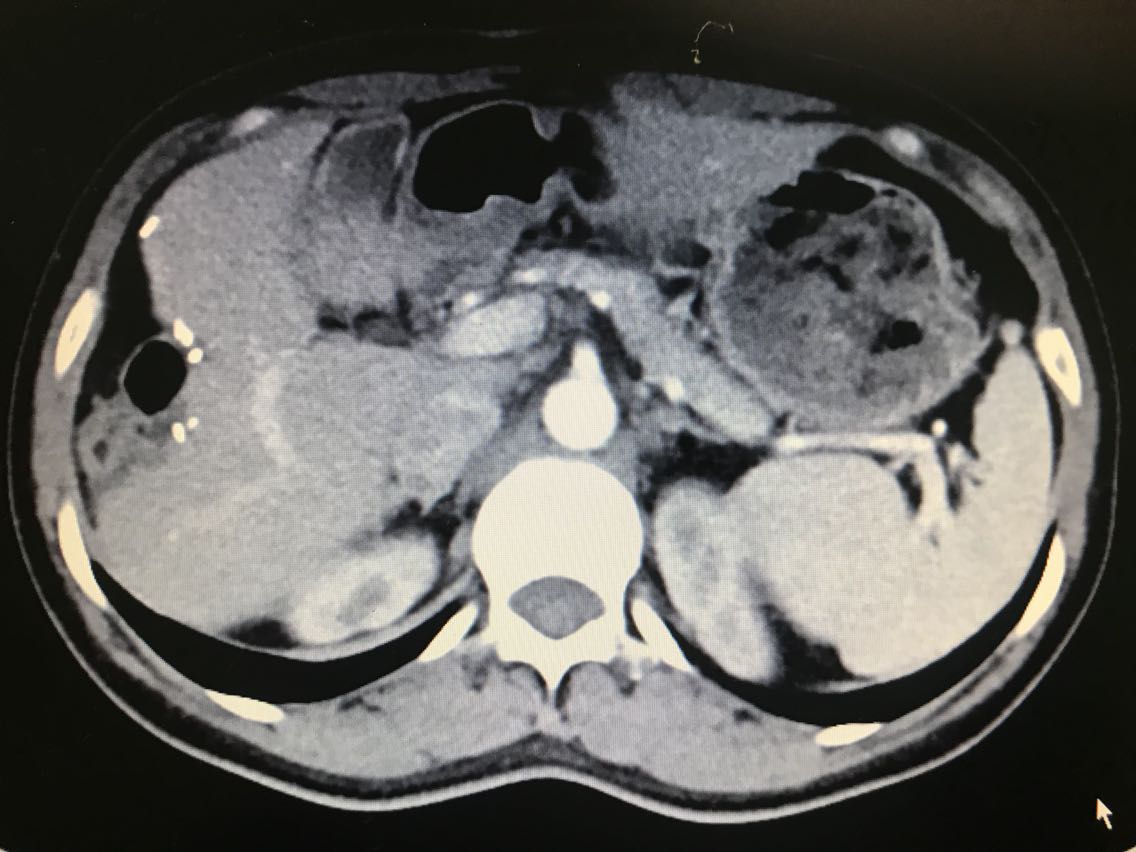

查体无特殊。 辅助检查: 全腹CT:右侧肾上腺占位。

诊断:1.原发性醛固酮增多症(右侧优势侧)2.右侧肾上腺结节 治疗:腹腔镜右肾上腺肿瘤切除术 术中见:右侧肾上腺肿物与肾周紧密粘连,金黄色,约1.0*1.8*1.0cm大小。剖视肿瘤为鱼肉状实性肿物。